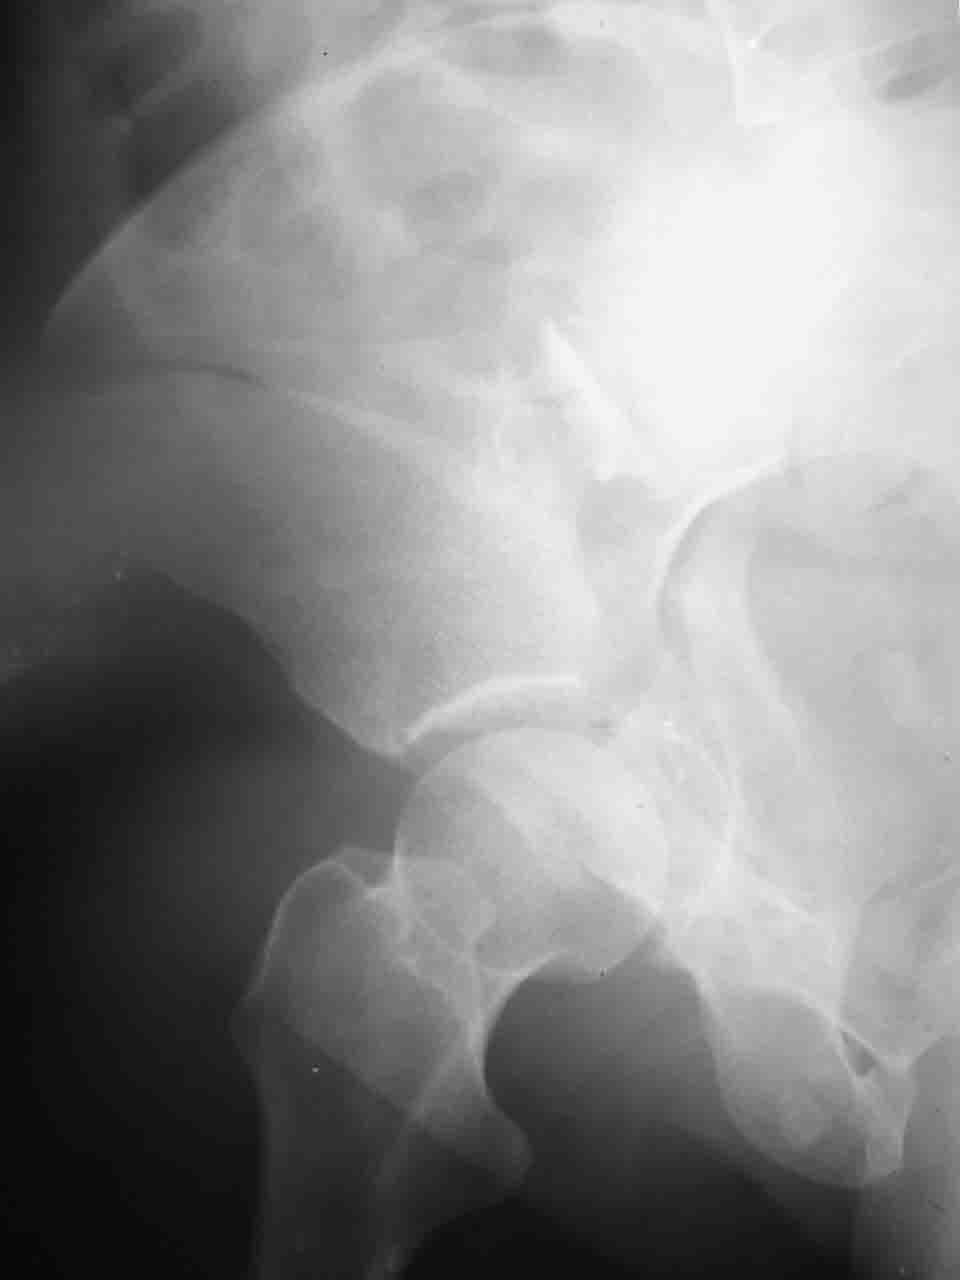

Спасибо за комментарии и рекомендации. Откровенно говоря, больного я прооперировал на прошлой неделе, через 5 дней после аварии и проблем с ним пока никаких нет, на удивление при достаточно обширной диссекции (илиофеморальный доступ) болей практически нет, так что больной самостоятельно садится в кровати, выполняет активные движения в оперированном суставе, сгибая до 60 градусов пока, далее с ассистенцией.

Причиной обращения к сообществу были возникшие непосредственно после операции сомнения и разочарования полученным качеством репозиции: а надо ли было трогать перелом вообще, репозиция передней колонны технически была очень сложна для меня, хотя реконструкции была в той же последовательности, что Д-р А.В.Рунков рекомендовал, в какой-то момент безуспешных манипуляций стал думать о *вторичной конгруэнтности*, которую не так давно обсуждали на

форуме и скелетном вытяжении. С репозицией и фиксацией задней колонны и отдельно задне-верхней стенки впадины проблем не возникло. Послеоп. Рг граммы в приложении. Если возникнут какие-либо дополнения или поправки - был бы признателен.